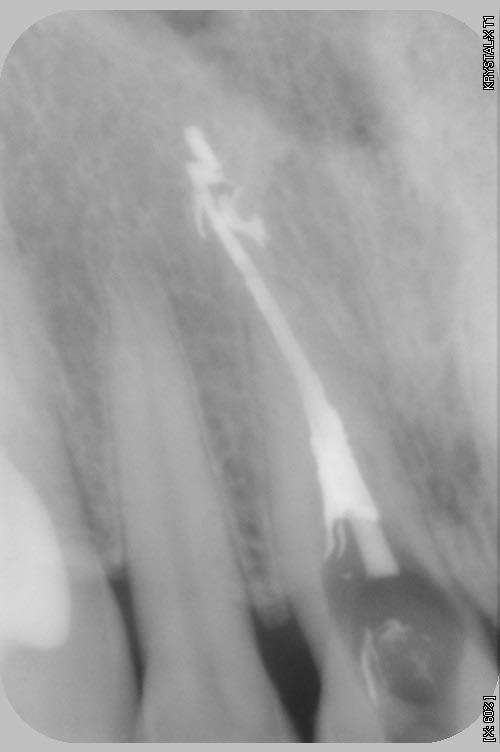

Comme l'a dit "dent 2669" c'est une résorption cervicale externe.

Le point d'entrée est vestibulaire ou palatin (je parierais pour palatin) ce qui donne cette impression de résorption interne centrée sur le canal. Comme l'a très bien expliqué "dent 2669" , la pré-dentine est visible autour du canal, c'est ce qui confirme que c'est une résorption externe.

L'endo est quasi impossible à faire car la résorption va se mettre à saigner dès qu'il y aura une effraction de la zone résorbée et il sera impossible de sécher le canal.

Faire un CBCT ne changera rien au pronostic de cette dent qui est condamnée. Par contre, cela permet de montrer ce qui se passe au patient qui comprendra mieux la nécessité d'extraire sa dent.

Me trompe-je?

L'envahissement canalaire m'évoque bien plus une origine interne. (quoi qu'elle ne change rien au pronostic)

Une externe, en terme d'image radio, c'est une carie basse, éventuellement avec de larges plages radiculaires, tu n'as pas cet élargissement canalaire.